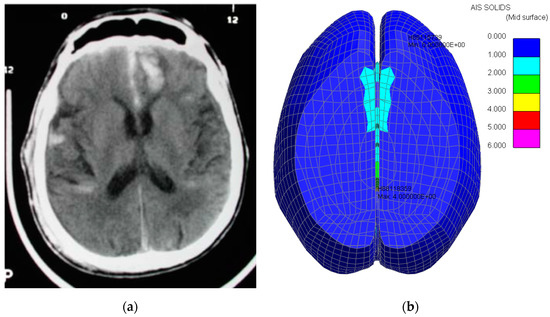

Figure 14.

First Accident. Brain trauma (coup). Comparison between CT scan [16] (a) CT Scan (coup) and computer predictions (b) Computer Simulation (coup).

Figure 15.

First accident. Brain trauma (contre-coup). Comparison between CT scan [16] (a) CT Scan (contre-coup) and computer predictions, (b) Computer Simulation (contre-coup).

In the computer model, there is evidence of trauma near the contact area between the head and the wooden block. The computer model suggests the same location as the CT scan.

The computer model also suggests trauma on the other side of the brain, as per the CT scan.

In the CT scan information provided in the paper [1], the location of the slides was not provided; hence, it is not possible to categorically assert whether the comparisons are exact. Nevertheless, the trauma pattern from Figure 16 is consistent with what has been reported.